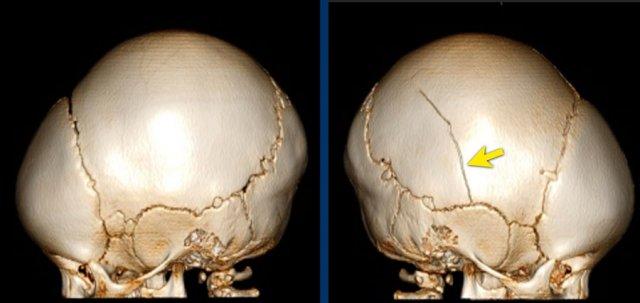

Gãy xương sườn

Trong hành vi lắc mạnh, đứa trẻ bị giữ rất chặt quanh ngực và bị siết chặt trong khi bị lắc.

Điều này nén các xương sườn theo hướng trước-sau và có xu hướng làm gãy chúng ở vị trí gần chỗ bám vào đốt sống và ở phía bên, nơi chúng gần như bị gập đôi.

Do cơ chế chấn thương đặc thù này, gãy xương sườn bên và sau có độ đặc hiệu cao đối với lạm dụng.

Hồi sức tim phổi hiếm khi, nếu không muốn nói là không bao giờ, là nguyên nhân gây ra những gãy xương như vậy.

Những gãy xương sườn này ở trẻ bị lạm dụng có thể được phát hiện tình cờ trên phim X-quang ngực được chụp vì lý do khác, chẳng hạn như đánh giá viêm phổi.

Gãy xương sườn có độ đặc hiệu cao đối với lạm dụng.

Trong một nghiên cứu tại Hà Lan, tổng cộng 254 gãy xương được tìm thấy trong 56 trường hợp chấn thương đầu do lạm dụng. Tỷ lệ gãy xương sườn và gãy xương hành xương cực kỳ cao (tài liệu tham khảo).

Gãy xương sườn gặp khó khăn tương tự như tổn thương hành xương ở chỗ chúng dễ bị bỏ sót trên phim X-quang.

Trong giai đoạn cấp tính, chúng không rõ ràng trên phim X-quang vì ít có sự di lệch.

Chúng thường được xác định trên phim khảo sát xương toàn thân lặp lại khi các gãy xương đang trong giai đoạn lành, biểu hiện bằng hình ảnh can xương.